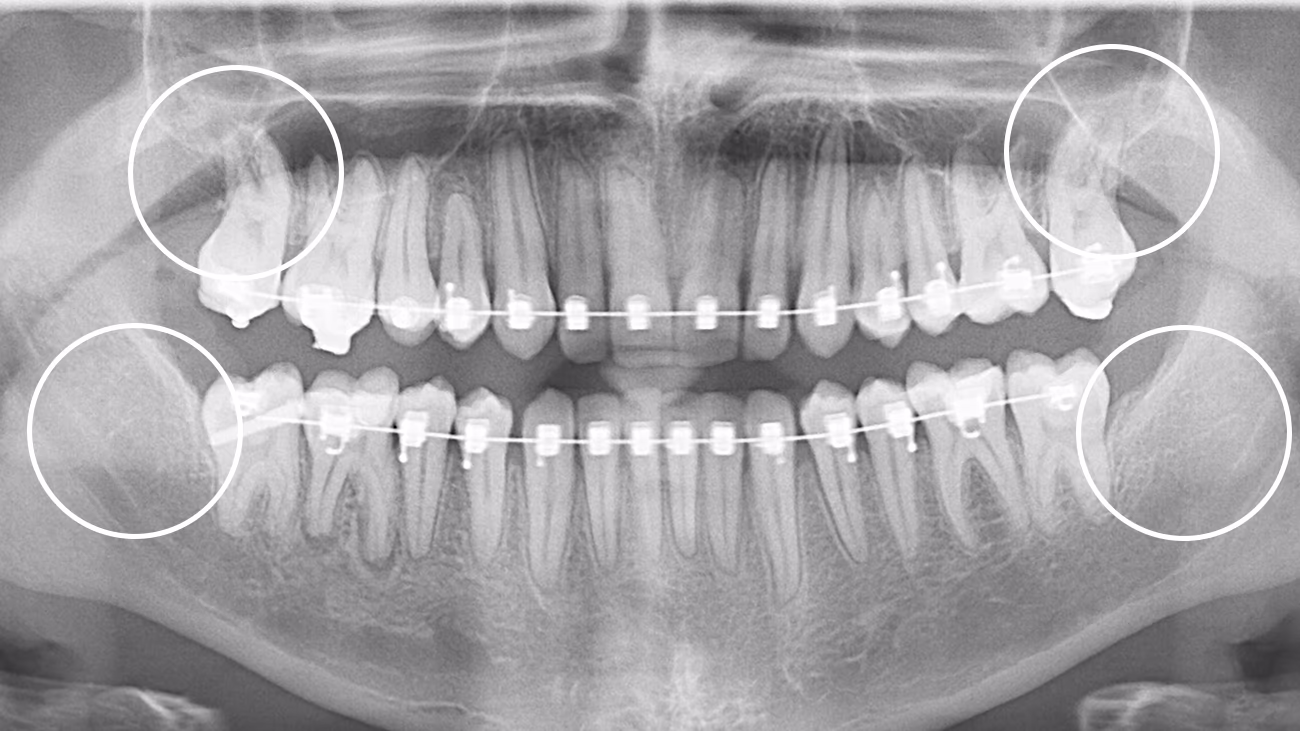

Так. КТ є обов’язковою для точного та безпечного видалення зуба мудрості.

3D-діагностика дозволяє визначити:

• положення зуба

• напрямок росту

• особливості коренів

• близькість до нижньощелепного нерва або верхньощелепної пазухи

У Sergatiy Dental Clinic КТ є обов’язковою перед видаленням зуба мудрості. Без КТ значно підвищуються ризики ускладнень.